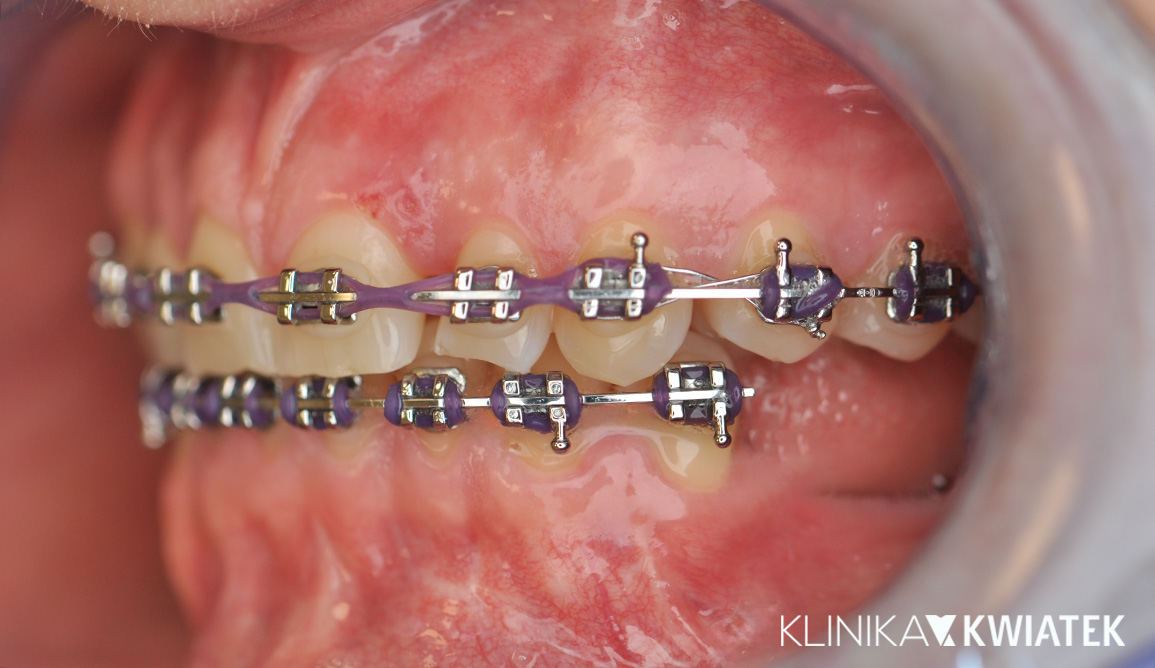

PRZED

Pan Jakub zgłosił się do kliniki z wadą zgryzu oraz licznymi problemami wynikającymi z nieprawidłowego ustawienia zębów. Leczenie wymagało współpracy specjalistów z kilku dziedzin stomatologii, precyzyjnego planowania oraz konsekwentnej realizacji kolejnych etapów terapii.

Dzięki ogromnej determinacji Pacjenta, który pomimo dużej odległości regularnie przyjeżdżał na zaplanowane wizyty, możliwe było przeprowadzenie kompleksowego leczenia, którego efektem jest doskonale zbalansowany zgryz oraz spektakularna i w pełni naturalna metamorfoza uśmiechu.